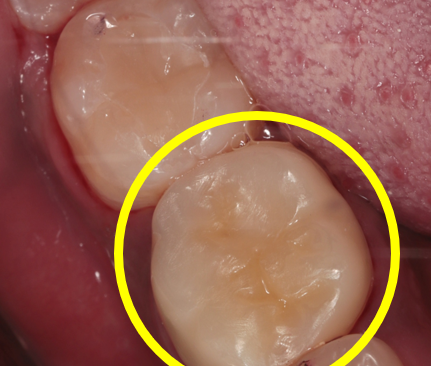

왼쪽 위 대구치 치료 전후 사진입니다.

충치의 범위가 넓기 때문에 레진으로 치료를 하기가 어려워 세라믹 인레이(부분보철)로 진행했습니다.

치료 후에는 완벽하게 수복이 되어 치아 내부를 보호하고 있는 모습을 보실 수 있습니다.